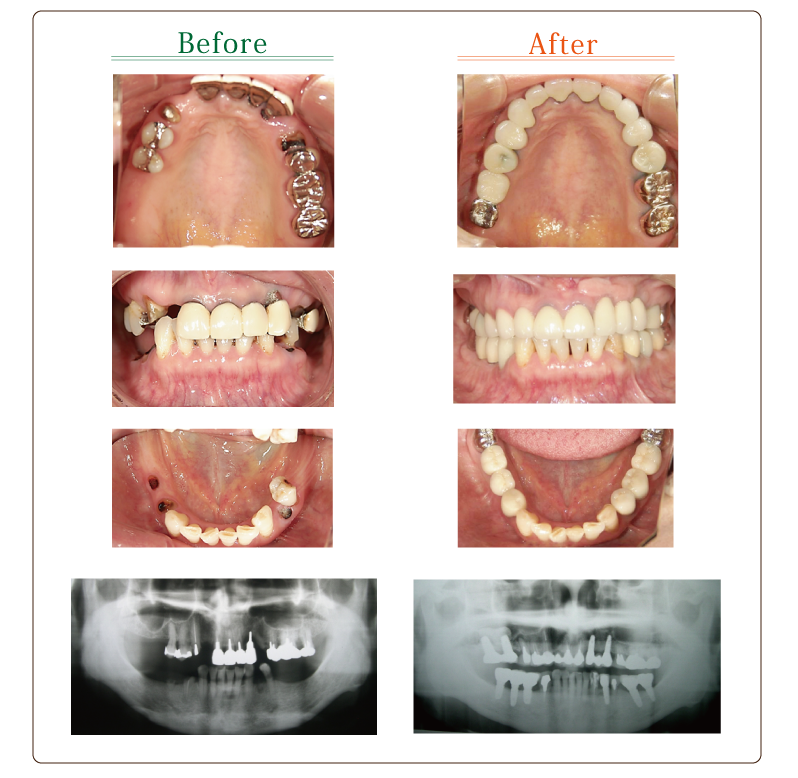

[ CASE1 ] インプラントとインプラント周囲の骨造成および歯肉移植等を用いて咬合再構成を行ったケース